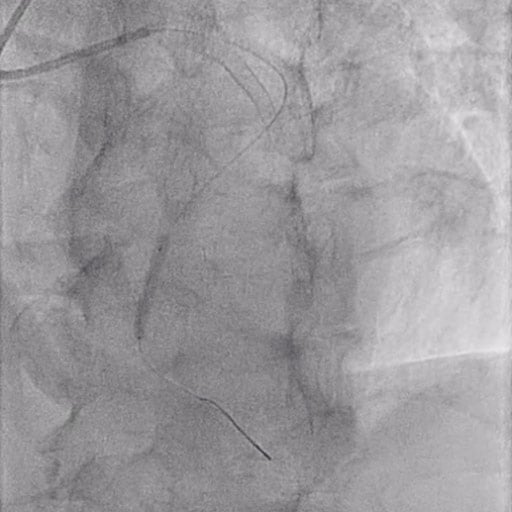

Figure 3: DCB inflation

In this case, a sirolimus drug-coated balloon catheter 3.0 x2 5mm was inflated for 1 min at 10 ATM.

After positioning the device at the target lesion, inflate it to 6-8 ATM and maintain inflation for at least 1 minute.

Once a satisfactory result is achieved in lesion preparation (similar to stent-like outcomes), DCB angioplasty can be performed.